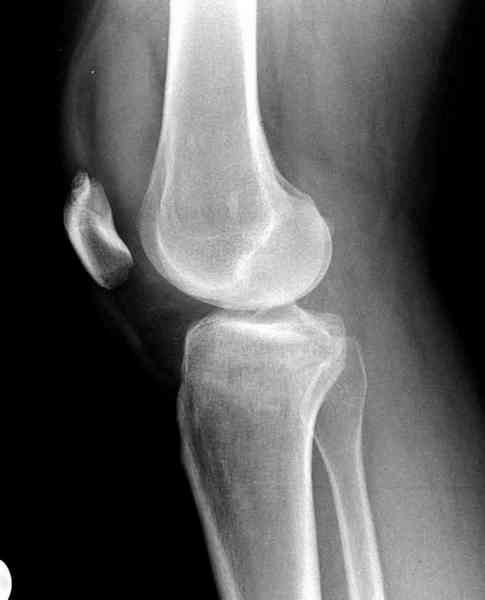

тоже склоняюсь в пользу АВФ ,однако остаётся не решенным вопрос с проксимальным эпиметафизом.Или вы считаете что можно пренебречь проседанием наружного мыщелка?

Как всегда прекрасная презентация. Совершенно согласен с необходимостью сохранять мениск и вообще согласен со всем, кроме одного. Фиксация должна проводиться после правильно выполненной репозиции. Главная цель репозиции - это восстановить высоту наружного мыщелка. В норме наружный мыщелок выше внутреннего на 4-5 мм на снимке в переднее заднем направлении АР.

Необходимость репозиции возникает при снижении высоты от 3 до 5 мм по разным источникам. По моему опыту 4 мм. Если не восстановить высоту мыщелка возникает вальгизация коленного сустава с относительным расслаблением передней крестообразной связки. При этом развивается нестабильность коленного сустава из-за недостаточности ПКС.

По этому если фрагмент большой есть необходимость репозиции дистального угла и фиксация пластинкой против соскальзывания ANTIGLIDING PLATE. Если перелом фрагментарный? то очень помогают описанные субхондральные шурупы RAFT, но

чтобы сохранить высоту суставной площадки шурупы одним концом должны опираться на пластинку а другим - на кортекс по внутренней стороне. Идеально сочетание ANTIGLIDING BUTRESS PLATE + RAFT SCREWS.